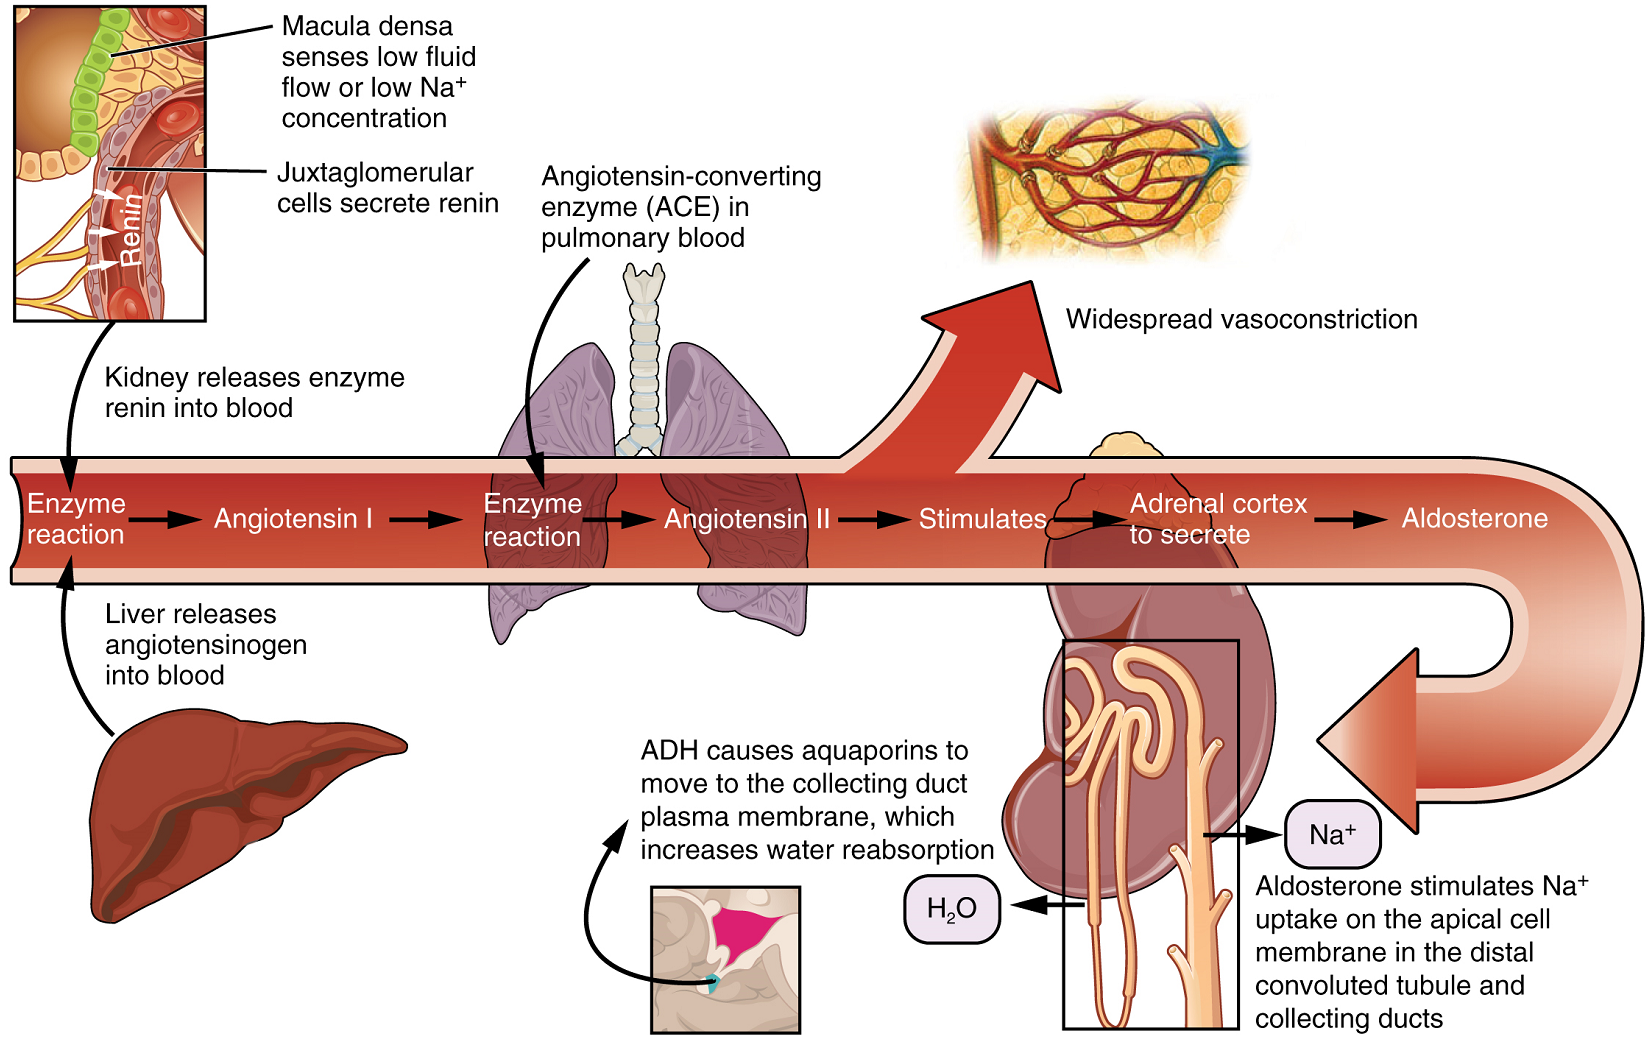

Aldosterone is a hormone produced by the cortex of the adrenal glands. The control of aldosterone is complex (Figure 11). One mechanism involves detection of a decrease in blood pressure by certain cells in the kidney, resulting in the release of the enzyme renin. This ultimately leads to the production of Angiotensin II, which stimulates the adrenal cortex to produce aldosterone. A second mechanism involves potassium ion concentration. An increased in K+ concentration in extracellular fluid directly stimulates aldosterone secretion by the adrenal cortex.

Aldosterone acts on the cells lining the distal convoluted tubule and the collecting duct to promote, simultaneously, active reabsorption of Na+ from the tubules and active secretion of K+ into the tubules. As Na+ is pumped from the forming urine, water is passively recaptured for the circulation; this preservation of vascular volume is critically important for the maintenance of a normal blood pressure. As an extremely potent vasoconstrictor, angiotensin II functions immediately to increase blood pressure. It also stimulates aldosterone production, which provides a longer-lasting mechanism to support blood pressure by maintaining vascular volume (water recovery).

While antidiuretic hormone is primarily involved in the regulation of water recovery, aldosterone regulates Na+ recovery. When aldosterone output increases, more Na+ is recovered from the forming urine and water follows the Na+ passively. As the pump recovers Na+ for the body, it is also pumping K+ into the forming urine, since the pump moves K+ in the opposite direction. When aldosterone decreases, more Na+ remains in the forming urine and more K+ is recovered in the circulation.